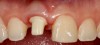

Fig 8. Extraction site No. 8 after atraumatic removal of the tooth.

Figure 8

Fig 9. Final custom abutment for tooth No. 8 in place with a provisional resin restoration that had been milled before surgery.

Figure 9

Plugging into digital workflows provides opportunities to integrate CAD/CAM technologies at every step of the treatment process for dental implants. In another example, a patient presented with a failing tooth No. 8 (Figure 6 and Figure 7). After discussing treatment options, the patient chose to forgo any treatment to address tooth and soft-tissue asymmetries and wanted to proceed with a dental implant-supported restoration without additional treatment. After integrated 3-dimensional planning, the tooth was extracted, and then an implant and the final custom CAD/CAM abutment (titanium base with zirconia supra-structure) were placed with a provisional restoration in the same visit (Figure 8 and Figure 9). Soft-tissue grafting was also done at the same visit to address the deficient buccal tissue height on No. 8 (Figure 10). At 3 months, the patient presented for the final restoration, with excellent healing around the implant (Figure 11) and soft-tissue healing guided by the custom abutment (Figure 12).